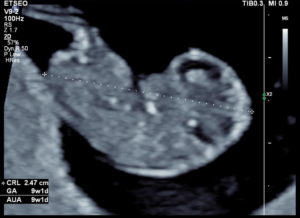

ETSEO (13 weken echo) 12+ 3 – 14+3 weken

De 13 weken echo is een medische echo. Deze echo wordt ook bij ons op de praktijk aangeboden door een echoscopiste die gespecialiseerd is in het maken van deze medische echo. Bij deze echo wordt er gekeken of je baby geen lichamelijke afwijkingen heeft. Je baby wordt van top tot teen nagekeken om te zien of alle organen en structuren zich goed ontwikkelen. Deze echo duurt wat langer, circa 30 – 45 minuten. Het verzoek is om bij deze echo geen kinderen onder de 12 jaar mee te nemen, omdat de echoscopiste zich goed moet kunnen concentreren.

Bij dit onderzoek is het helaas niet mogelijk om een uitspraak te doen over het geslacht, dit komt omdat de 13 weken echo een medisch onderzoek is en niet bedoeld is als geslachtsecho, daarnaast is bij 13 weken het nog niet geheel zeker wat het geslacht is. Lees hier meer informatie over de 13 weken echo. Als je deze echo wenst te laten verrichten, moet je een toestemmingsformulier tekenen omdat deze echo nog wordt gedaan op basis van een wetenschappelijke studie.